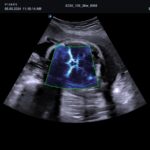

El X-CUBE 60 se desarrolló para brindar un entorno de trabajo cómodo a la usuaria. El rendimiento óptimo de imagen se logra gracias a la arquitectura X+, el motor de imágenes de alta resolución de la serie X-CUBE, para un diagnóstico fiable de diversas enfermedades. Repetir el diagnóstico a diario agota al personal médico. Diversas funciones de medición automática, que se adaptan al flujo de trabajo del usuario, reducen el tiempo de diagnóstico, y la pantalla táctil de mayor tamaño y el panel de control intuitivo reducen la fatiga. Además, su tamaño compacto y versátil permite un uso eficiente del espacio en la sala de escaneo.

| Arquitectura del Sistema: | Arquitectura X+, Power View, FleXcan, SensitiView, X+ Cristal Signature, X+ Fit, Optimal Imaging Suite |

| Software Disponibles OB/GIN: | 3D/4D convexo y endocavitario, Live HQ, Volume Advance, Auto Translucencia Nucal (NT), X+ Auto Biometry, X+ Follicle, Silhouette View |